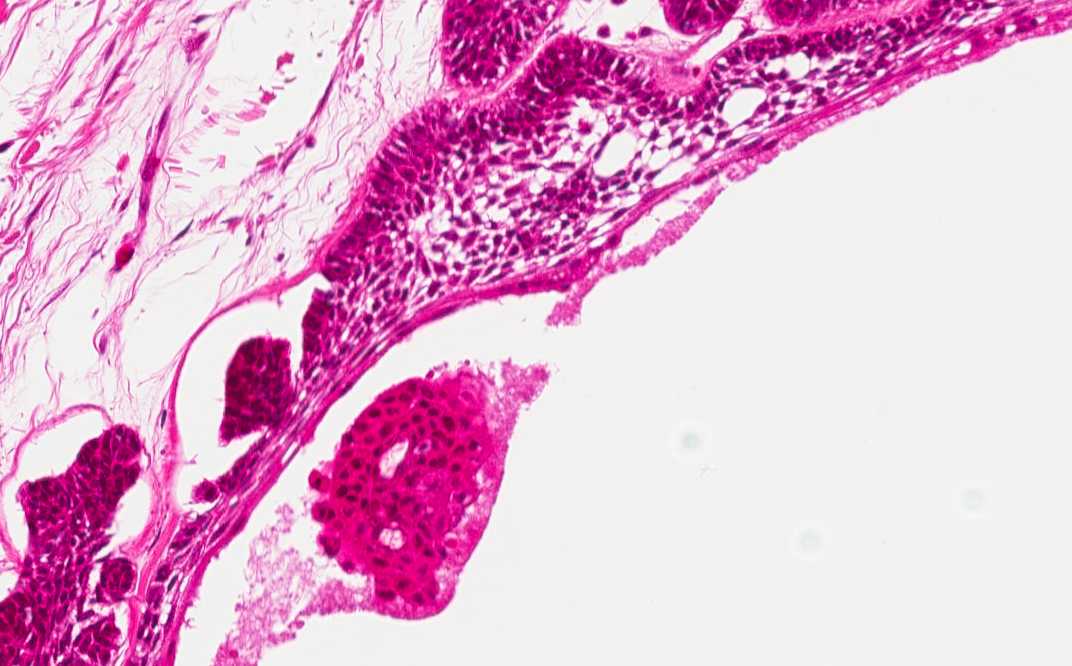

Area 1: Note that the cords and nests contains peripherally located palisading epithelial cells with reversed polarity. These cells resembles the ameloblasts of normal tooth formation. The stellate central cells resemble the stellate reticulum of the tooth germ.

Histologic Highlights of this Case:

• In Area 1, there are cords and nests of neoplastic cells infiltrating the fibrous stroma. At the periphery of the cell nests are palisading, elongated columar cells with reversed polarity of nuclei (nuclei are located away from the basement membrane). The center of the cords and nets are occupied by stellate cells which occupy the center of the cell nests.

• The overall nuclear features are bland and without significant pleomorphism or high grade atypia. Mitotic figures are not readily seen.

• Note that the specimen appears more eosinophilic than other specimens being shown in this program. This is because the specimen has to be decalcified before examination and slightly over decalcified specimens often appear more eosinophilic and the nuclear details are not as well preserved.

• The histologic appearance is also characteristic. Recurrence is common. There are islets or plexiform arrangement of epithelial cells.  The cells resemble the enamel organ of the developing tooth germ. Typically the epithelial islets consist a peripheral layer of cuboidal or columnar cells which may be rather like ameloblasts and a central area of cells similar to stellate reticulum.

• Strongly eosinophilic degenerative substance which are PAS(+) can be seen at the center of the nests. Squamous metaplasia may be extensive enough to fill up the entire cell nest and such histologic picture may suggest squamous cell carcinoma on casual examination. There may be calcifications.